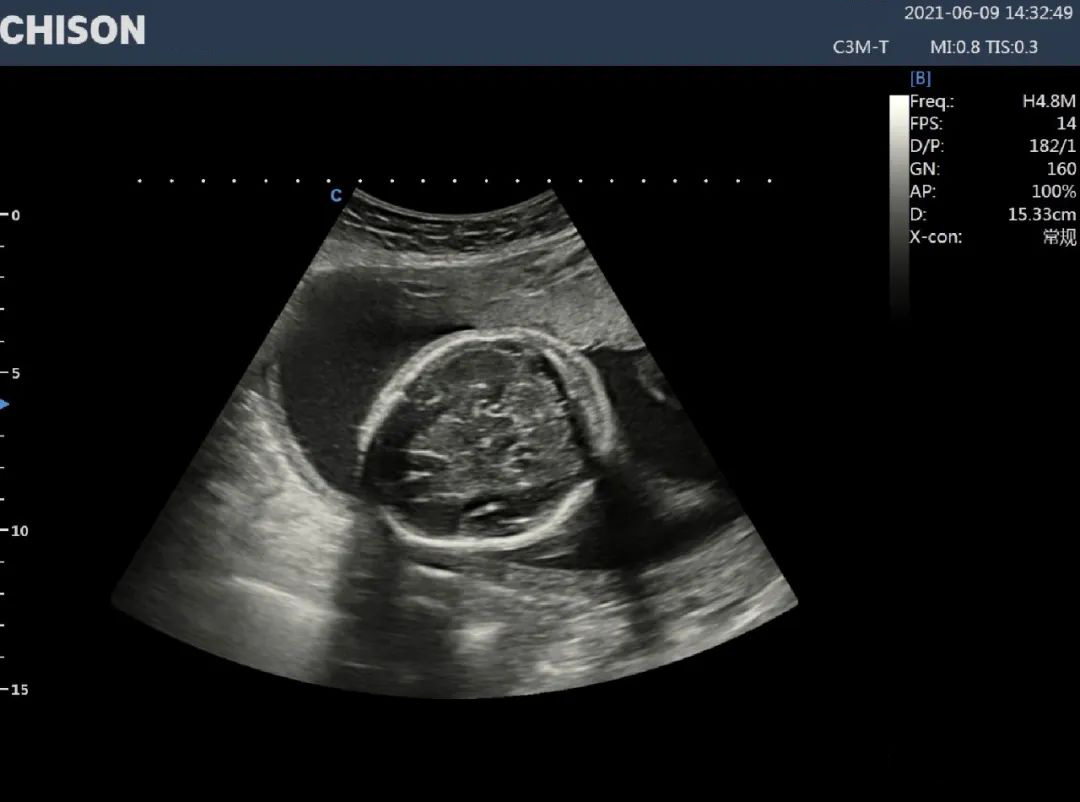

A 27-year-old female with full term pregnancy with a complaint of abdominal pain with massive vaginal bleeding.

An ultrasound image shows the placenta covering the internal orifice of the cervix and the fluid pocket near the margin of the cervix of about 27*18mm.

Complete placenta previa with placental abruption.